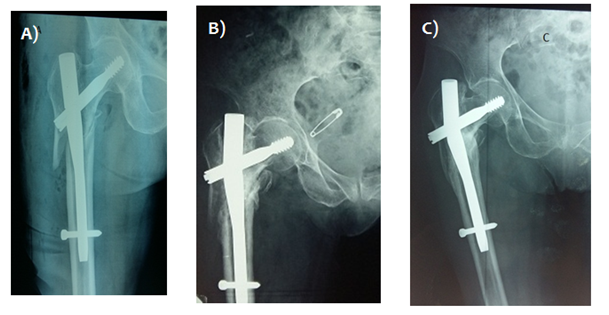

6 cases (1.5%) with cervical screw cut-out were recorded, with immediate postoperative radiography showing bad positioning: cervical screw placement was either too superior or posterior and sometimes even too short. Two cases with acetabular penetration required a total hip arthroplasty, and a single case of revision using a 95 ° dynamic condylar plate screw. A case of early secondary displacement of sub trochanteric fracture treated with standard gamma nail underwent revision using a 95 ° dynamic condylar with a favorable outcome (Figure 3). Two cases (0.5%) that failed to unite underwent revision using the conventional 95° condylar screw plate system. One entailed a sub trochanteric fracture treated with a long gamma nail which required revision surgery after 6 months using a condylar plate screw with iliac crest bone graft. The second case was marked by implant failure and breakage after 5 months requiring revision using conventional dynamic condylar screw system (Figure 3). However, another case of implant breakage with radiological progression of callus was closely monitored and eventually united after 6 months without reoperation (Figure 4).

Figure 4 A) Immediate postoperative x-ray show AO/OTA 3.1 A3 fracture treated with standard gamma nail. B) x ray image at 4 months postoperative showing nail breakage. C) x-ray image at 6 months showing bony union despite implant breakage.